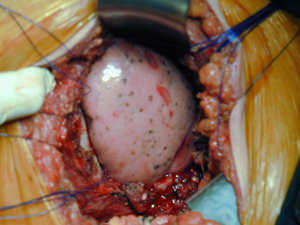

Εικόνα 2

Διεγχειρητική φωτογραφία. Έλλειμμα στο θωρακικό τοίχωμα, μετά από την αφαίρεση όγκου θωρακικού τοιχώματος. Διακρίνεται ο υποκείμενος πνεύμονας και φαίνονται οι άκρες των αφαιρεθέντων πλευρών.